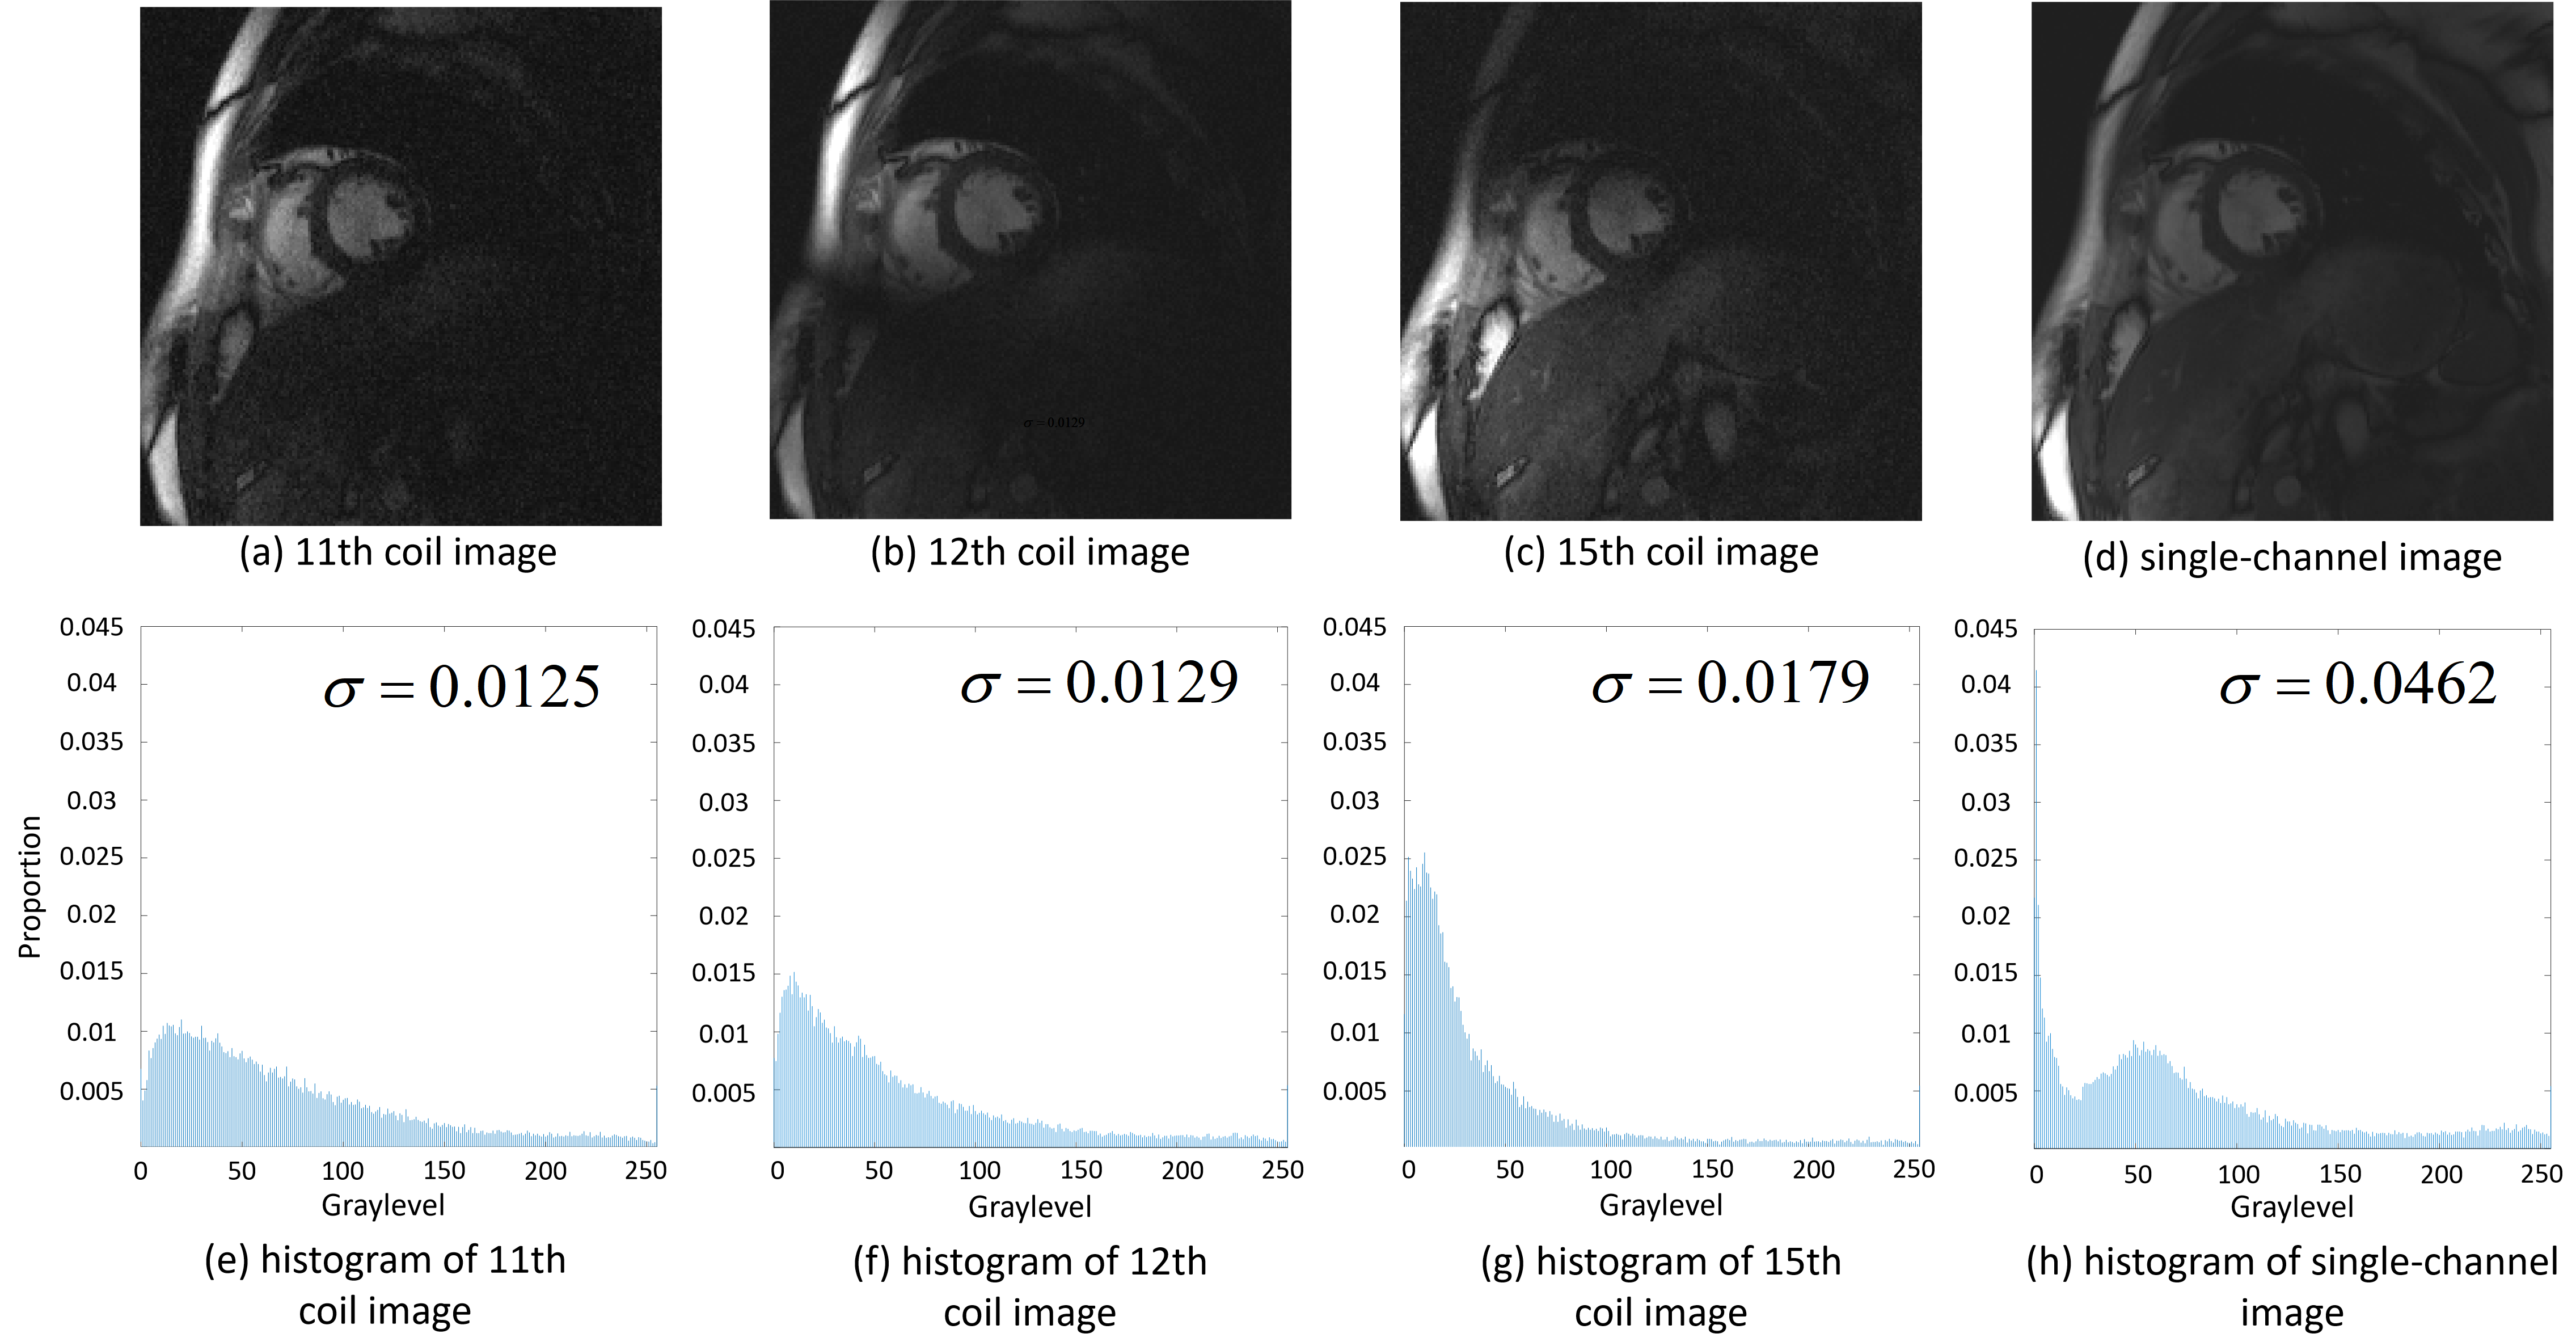

Unlike other methods [22, 23, 24] that use single-channel signals as input and output, our parallel network focuses on a multichannel scenario and could explore coil correlations. Another advantage of a multichannel approach to coil images is that single-channel data have a complicated distribution [35], which undoubtedly increases the difficulty of network learning. We visualized the statistical distributions of the single-channel and multichannel coil images; statistical histograms of both are provided in Fig.4. The second moment, , which can measure the complexity of pixel histograms [36], is also given. Its calculation formula is as follows:

| (4) |

where is the value of the pixel , and is the number of pixels in the image. A larger indicates a more complex image. To fairly compare the second moments of these images, all images were normalized in our experiments. The statistical histogram and quantitative indicators show that each coil image from the multi-channel data has a simpler statistical distribution than does the combined single-channel image. In Section IV.A, we compare a single-channel model with a multichannel model under the proposed unsupervised framework and find that the multichannel model achieves better reconstruction results.

hlshow histograms of these images. The data are normalized to [0, 255] for convenient display. The second moment, , of each image is also given.